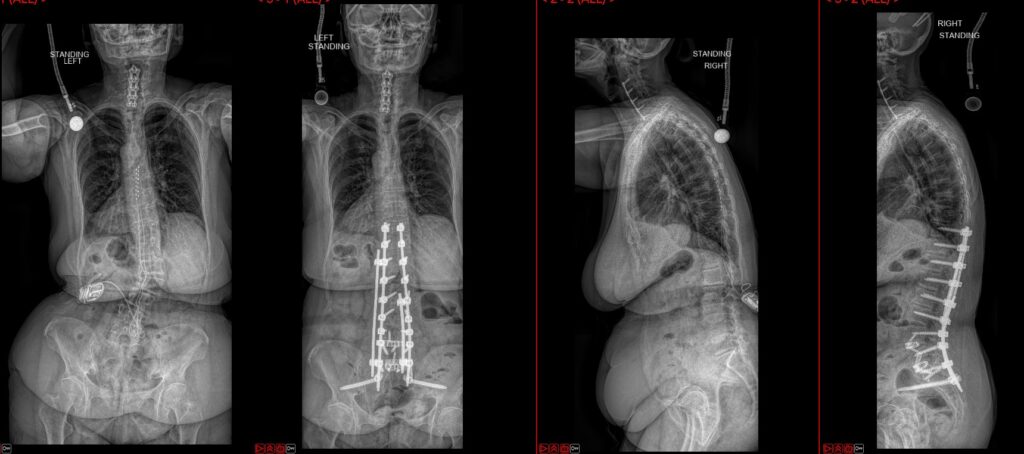

Deformity Surgery